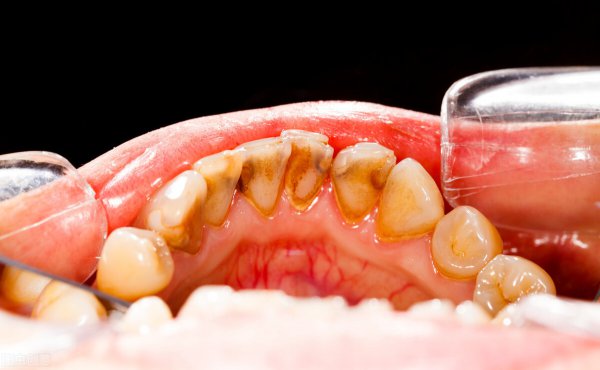

成年后的模样

75%的磷酸钙,15%~25%的水、有机物、磷酸锰、矿酸钙及微量的钾、钠、铁构成,呈黄色、棕色、或者黑色。

龈上牙结石,也叫可见牙结石,一般是覆盖在牙缝、牙背、牙根部,肉眼能看到。

龈下牙结石,也叫不可见牙结石,这种牙结石已经侵入到了牙龈下了,一般伴随有牙龈出血,肉眼不能看到。

0度:无软垢及牙结石。

1度: 少许软垢或牙结石,但未超过牙面的l/3。

2度:有牙结石,未超过冠面的1/3,有少量的龈下结石。

3度:牙结石不超过冠面的2/3,有较多的龈下结石。